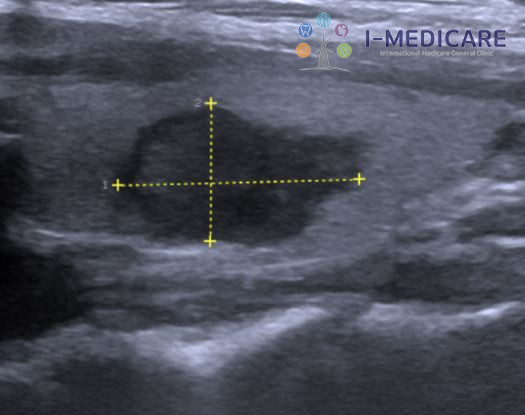

Phát hiện nốt giáp và đánh giá nguy cơ

Một trong những ứng dụng quan trọng nhất của là phát hiện và đánh giá các nốt giáp. Đây là tình trạng phổ biến, khi có đến 50-70% người trưởng thành có thể xuất hiện nốt giáp, dù phần lớn là lành tính. Siêu âm giúp bác sĩ xác định đặc điểm của nốt và ước lượng nguy cơ ác tính một cách chính xác.

Cụ thể, siêu âm tuyến giáp giúp:

• Xác định kích thước và vị trí nốt giáp, kể cả những nốt rất nhỏ mà sờ tay không phát hiện được.

• Đánh giá ranh giới, cấu trúc và mức độ vôi hóa của nốt.

• Phân tích tỷ lệ chiều cao, chiều rộng và mức độ tăng sinh mạch máu.

• Phân loại nguy cơ ác tính theo các hệ thống chuẩn hóa như TI-RADS.

Những nốt có ranh giới không đều, vôi hóa vi thể, cấu trúc đặc và tăng sinh mạch máu mạnh thường có nguy cơ ác tính cao. Ngược lại, nốt có ranh giới rõ, chứa nhiều dịch, không vôi hóa thường lành tính. Tuy nhiên, chỉ sinh thiết tế bào mới có thể xác định chính xác bản chất của nốt giáp.